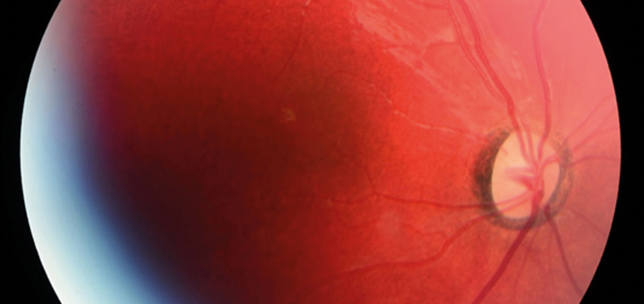

Unilateral central scotoma following dengue fever

Prabakaran Selvaraj

Shery Thomas

Isabel Ash

Arun Lakshmanan